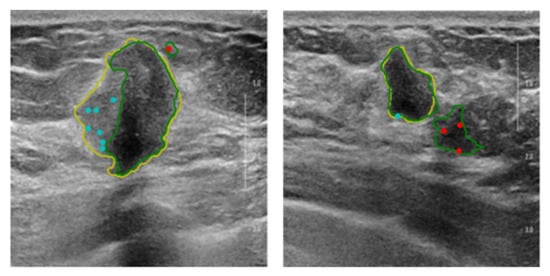

Figure 3 shows some examples of simulated interaction points in the training phase.

Figure 3. Examples of simulated interaction points in the training phase. The yellow and green lines are the contours of the ground truth and the previous segmentation, respectively. The cyan and red points are foreground and background interaction points, respectively.